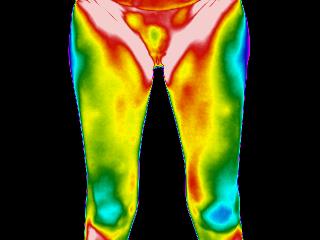

La thermographie vivante est une méthode d’imagerie fonctionnelle non invasive, sans contact, sans rayons, indolore, qui permet de visualiser la carte thermique du corps humain. Elle détecte les variations de température cutanée, révélatrices de phénomènes physiologiques internes : inflammation, surcharge fonctionnelle, tension musculaire, déséquilibres vasculaires, métaboliques ou neurologiques.

Elle révèle plutôt comment ces tissus fonctionnent en temps réel, en mesurant les émissions naturelles de chaleur générées par l’activité métabolique du corps.

La température cutanée que la caméra thermique capte n’est pas un simple reflet de la peau. Elle exprime les interactions profondes entre les systèmes vasculaire, neuromusculaire, inflammatoire et endocrinien.

Elle permet ainsi de détecter :

- Des zones de surchauffe (inflammation, surcharge fonctionnelle)

- Des zones de froid anormal (hypoactivité, trouble circulatoire, déconnexion neurovasculaire)

- Des asymétries thermiques révélant une compensation posturale ou une perturbation fonctionnelle

Un tissu qui souffre, qui s’emballe, qui ralentit ou qui compense ailleurs laisse toujours une empreinte thermique identifiable.